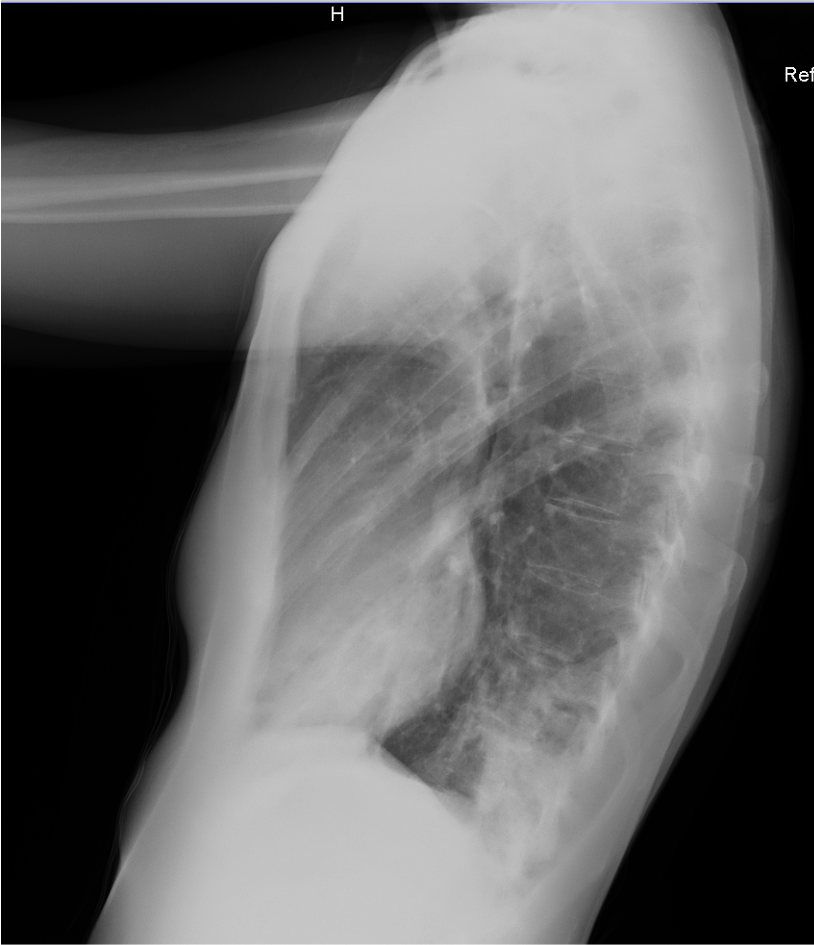

Mujer de 43 años, asma bronquial en tratamiento con broncodilatadores a demanda, acude por síntomas catarrales de 7 días de evolución, con empeoramiento progresivo con aparición de expectoración purulenta y pico febril en las últimas 24 horas, así como dolor pleuromecánico en hemitórax derecho, con disnea de esfuerzos. Normotensa, taquicárdica, afebril a su valoración y con saturación 95% basal. A la auscultación, crepitantes en base derecha. Analíticamente leve leucocitosis con neutrofilia y elevación de PCR (130,5 mg/L). Se realiza un electrocardiograma, que muestra una taquicardia sinusal, en otros; y una radiografía de tórax, en la que se aprecia un infiltrado en base derecha, sin derrame aparente.

Se completa estudio con ecografía pulmonar a pie de cama, que muestra Sliding conservado, con patrón de líneas B en base y campo medio derecho, con una pequeña consolidación subpleural en base derecha. En base izquierda, consolidación pulmonar, con hepatización, y derrame pleural asociado.

La ecografía pulmonar nos proporcionó hallazgos que no eran visibles en la radiografía simple, permitiendo una mejor clasificación de la severidad del cuadro de la paciente, adaptando la actitud clínica según los protocolos existentes.